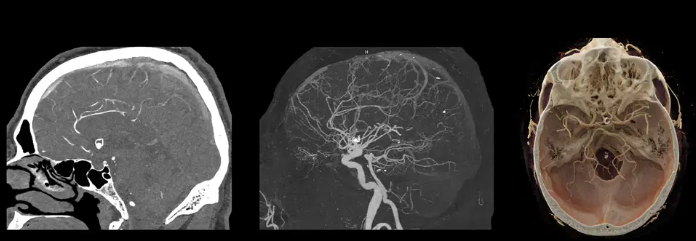

1. Photon-Counting CT (PCCT): A Nova Era da Tomografia

A TC convencional usa detetores de cintilação que convertem Raios-X em luz e depois em sinal elétrico. O Photon-Counting elimina essa etapa, convertendo os fótons de Raios-X diretamente em sinal elétrico.

Imagine um paciente com múltiplos stents coronários ou próteses metálicas. Na TC comum, o artefato de blooming (ofuscamento) impede-nos de ver o interior do vaso. Com o PCCT, a resolução espacial chega a 0.2mm.

Situação Real: "O radiologista pede para avaliar a patência de um stent de 2mm. No PCCT, você não precisa de filtros de reconstrução ultra-duros que aumentam o ruído; a própria natureza do detetor já fornece a nitidez necessária para separar o metal do contraste." Ressonância Magnética e Adenomiose